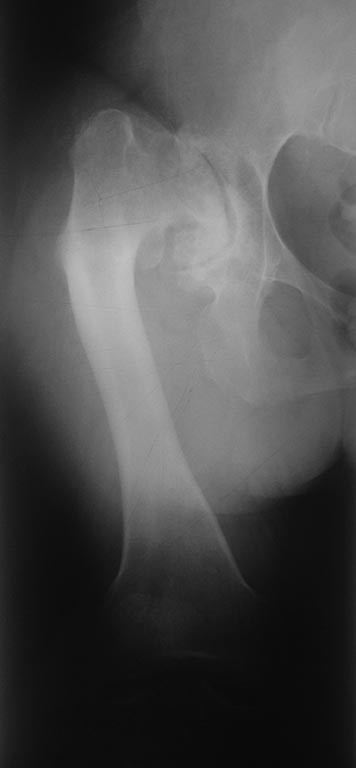

Пациентка 48 лет, врожденная аномалия скелета. В настоящее время

поступила с диагнозом:Диспластический коксартроз III ст справа, вывих

левого бедра (Crowe IV)/Гонартроз слева III. Варусные деформации обоих

дополненное скелетным вытяжением. Планируется: Первым этапом

эндпротезирование правого тазобедренного сустава с одномоментной

коррекцией варусной деформации. Вторым этапом